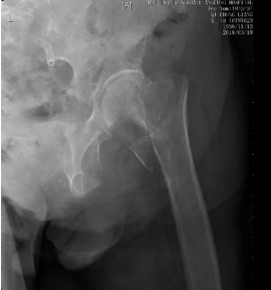

北京清华长庚医院肾内科(吕佳璇)北京清华长庚医院血透室的齐老,80岁,透析了11年,4个月前因急性胰腺炎和急性心肌梗塞刚出院,有继发性甲状旁腺功能亢进和肾性骨病。2周前在家不小心摔倒,疼痛难忍,不能动弹,被救护车送至他院,查体左下肢较对侧短缩2cm,髋关节压痛明显,强迫体位,X片诊断左股骨粗隆骨折,因年龄大、合并症多、心梗不超过6月,建议不适合手术,回家行保守治疗。

潘勇卫教授了解病情后马上安排齐老住院,联系心内科和麻醉科联合会诊,共同评估患者病情,研究手术方案,决定行股骨粗隆下骨折髓内针内固定术。透析室调整透析方案,手术前后给以枸橼酸透析保驾,手术仅用了一个小时,避免了手术并发症,齐老很快就下床活动了。